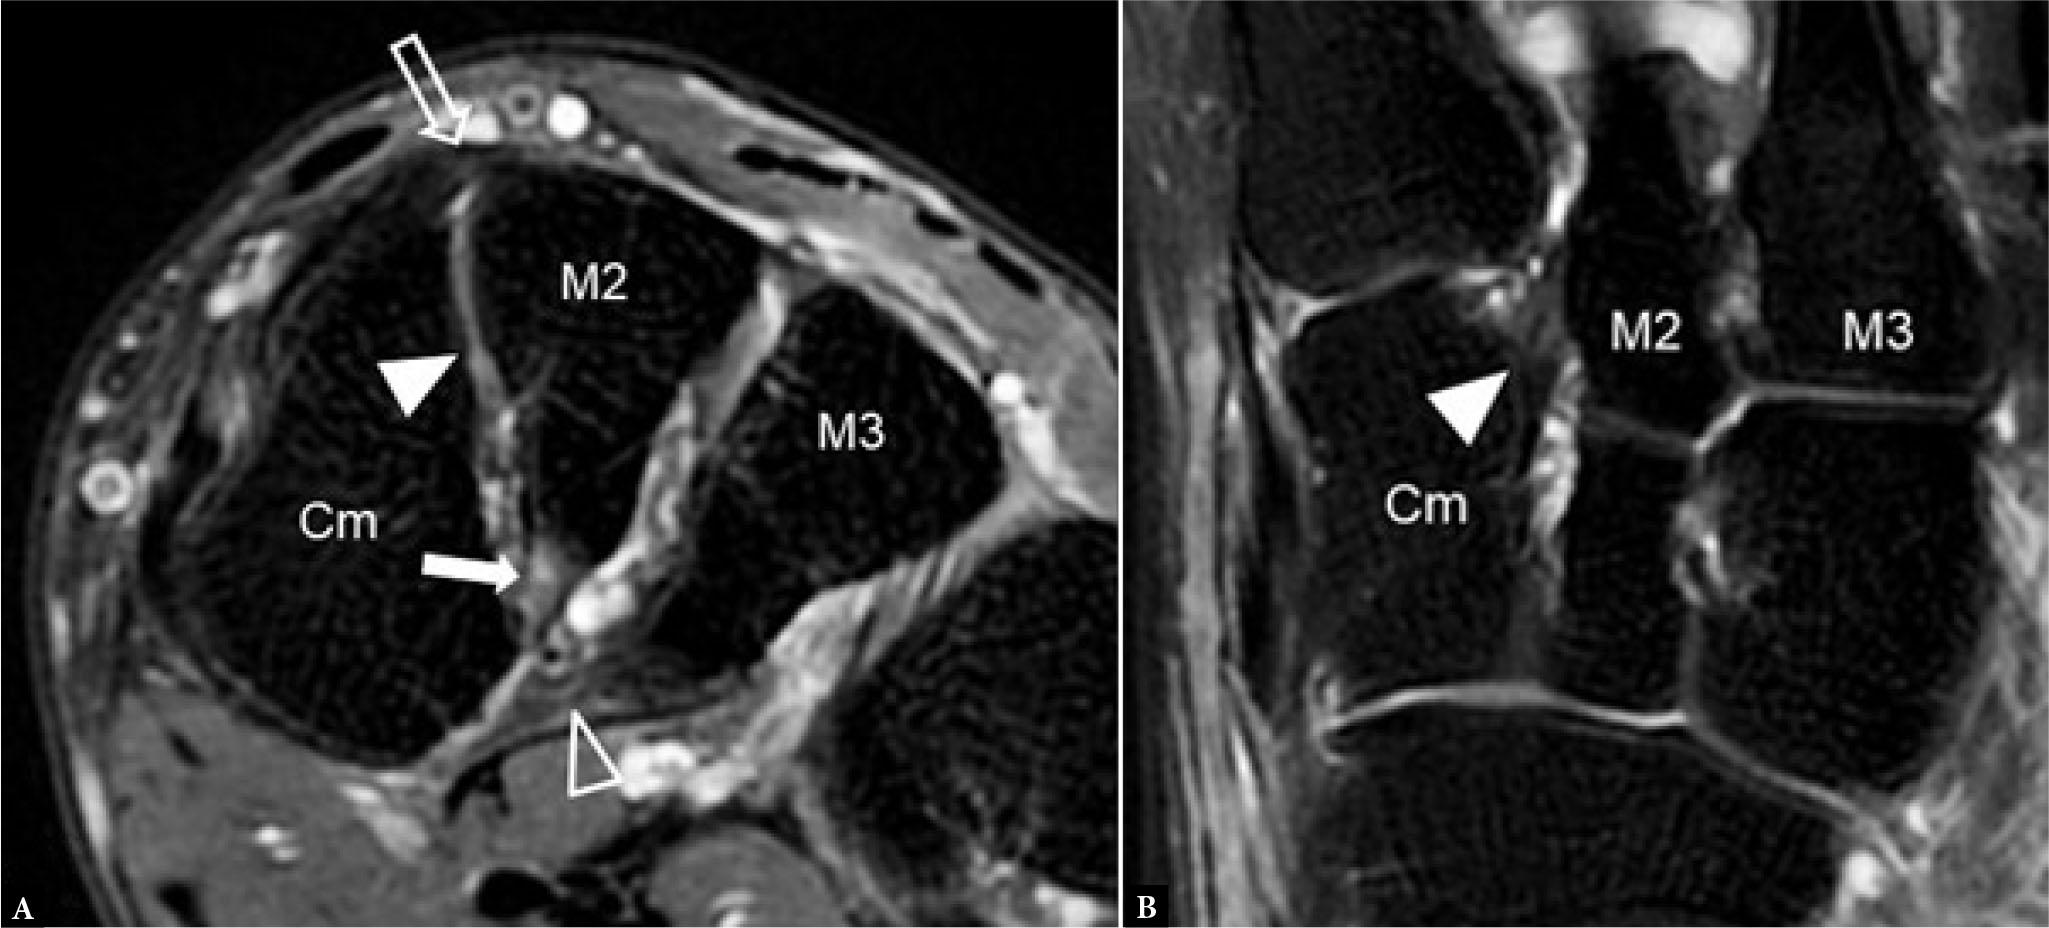

Fig. 8.

49-year-old man with medial forefoot pain following injury. Lisfranc injury was suspected clinically. T2-fat suppressed A. coronal MR image shows a moderately edematous cuneiform-2nd metatarsal ligament (arrow) without a discrete tear consistent with a moderate-severity sprain. The dorsal ligament (open arrow), interosseous Lisfranc ligament (closed arrowhead), and cuneiform-3rd metatarsal ligament (open arrowhead) are all intact. B. T2-fat suppressed axial MR image in the same patient shows the intact interosseous Lisfranc ligament (closed arrowhead)